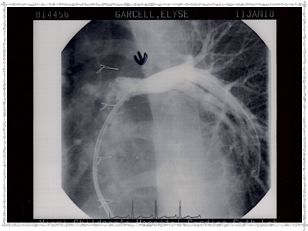

Second Catheterization — Dr. Danyal Khan

In 2010, Elyse underwent her second catheterization procedure, overseen by Dr. Danyal Khan at Miami Children's Hospital. The procedure focused on her pulmonary arteries, and these images show the before and after.

2010 - Before Procedure

Before the procedure